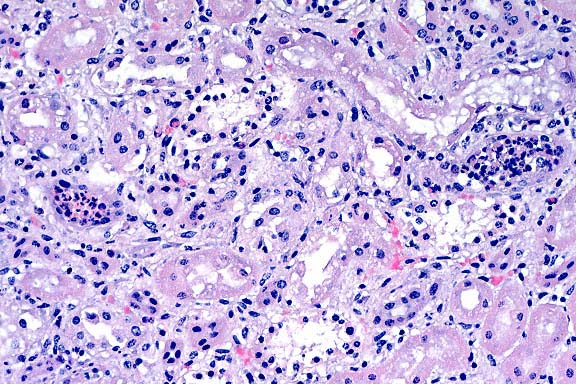

- The giant cell pneumonia seen in this case is typical of

SIVmac-induced giant cell pneumonia and is characterized by extensive

infiltration of alveolar septa and spaces by numerous macrophages

with abundant foamy cytoplasm and multinucleate giant cells of

macrophage-monocyte origin. The interstitial pneumonia with karyomegaly

and intranuclear inclusions is characteristic of cytomegalovirus,

a common secondary infection in SIVmac-infected animals. On transmission

electron microscopy, an unidentified cell in the lung was found

to contain an intranuclear inclusion body with peripheral clearing

of the nuclear chromatin. Dispersing the nuclear chromatin were

viral particles measuring 100 to 110 nm. The viral particle size

and morphology were consistent with those of the herpesviridae

group.

- Case 22-1. Lung. A syncytial giant cell is accompanied

by abundant foamy alveolar macrophages within and thickening

the septal walls (interstitial pneumonia).

- Additionally, there is multifocal thickening of alveolar

septa by neutrophils, macrophages, and type II pneumocytes. Pneumocytes

sometimes contain eosinophilic intranuclear inclusions that marginate

the chromatin, or large, basophilic inclusions that completely

fill the enlarged the nuclei. Alveoli sometimes contain large

multinucleate cells with abundant eosinophilic cytoplasm and

up to 15 peripheral nuclei. In addition, there are fewer multinucleate

cells with less cytoplasm and fewer, centrally located, nuclei.

The interstitial changes and multinucleate cells are most readily

observed at the interface of less affected lung parenchyma and

areas of consolidation.